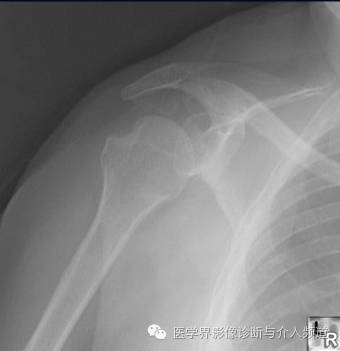

20、Trough 征

肱骨头前内侧骨折。受伤机制为肩关节后脱位时肱骨头撞击肩胛盂后缘造成。